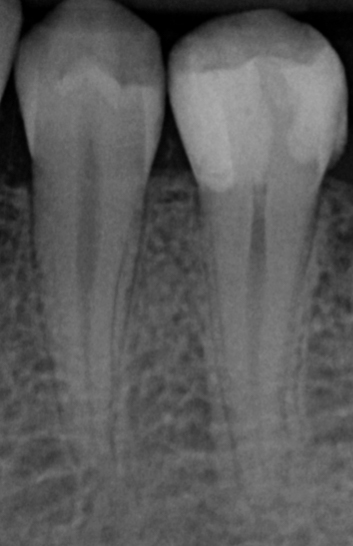

Hands-on training in het behandelen en restaureren van pulpa-exposities in molaren

De cursus bestaat uit een combinatie van interactieve theorie en praktische oefeningen. Er wordt gewerkt met preparatiemodellen waarin een diepe caviteit en pulpablootstelling wordt gesimuleerd.

• Biologie van de pulpa en criteria voor vitaliteit;

• Behandelopties bij diepe cariës en pulpa-expositie;

• Materialen: calciumhydroxide, MTA, Biodentine, bioceramieken;

• Preparatie van diepe caviteiten in molaren;

• De anatomie van het pulpadak en pulpakamer correct te herkennen en prepareren;